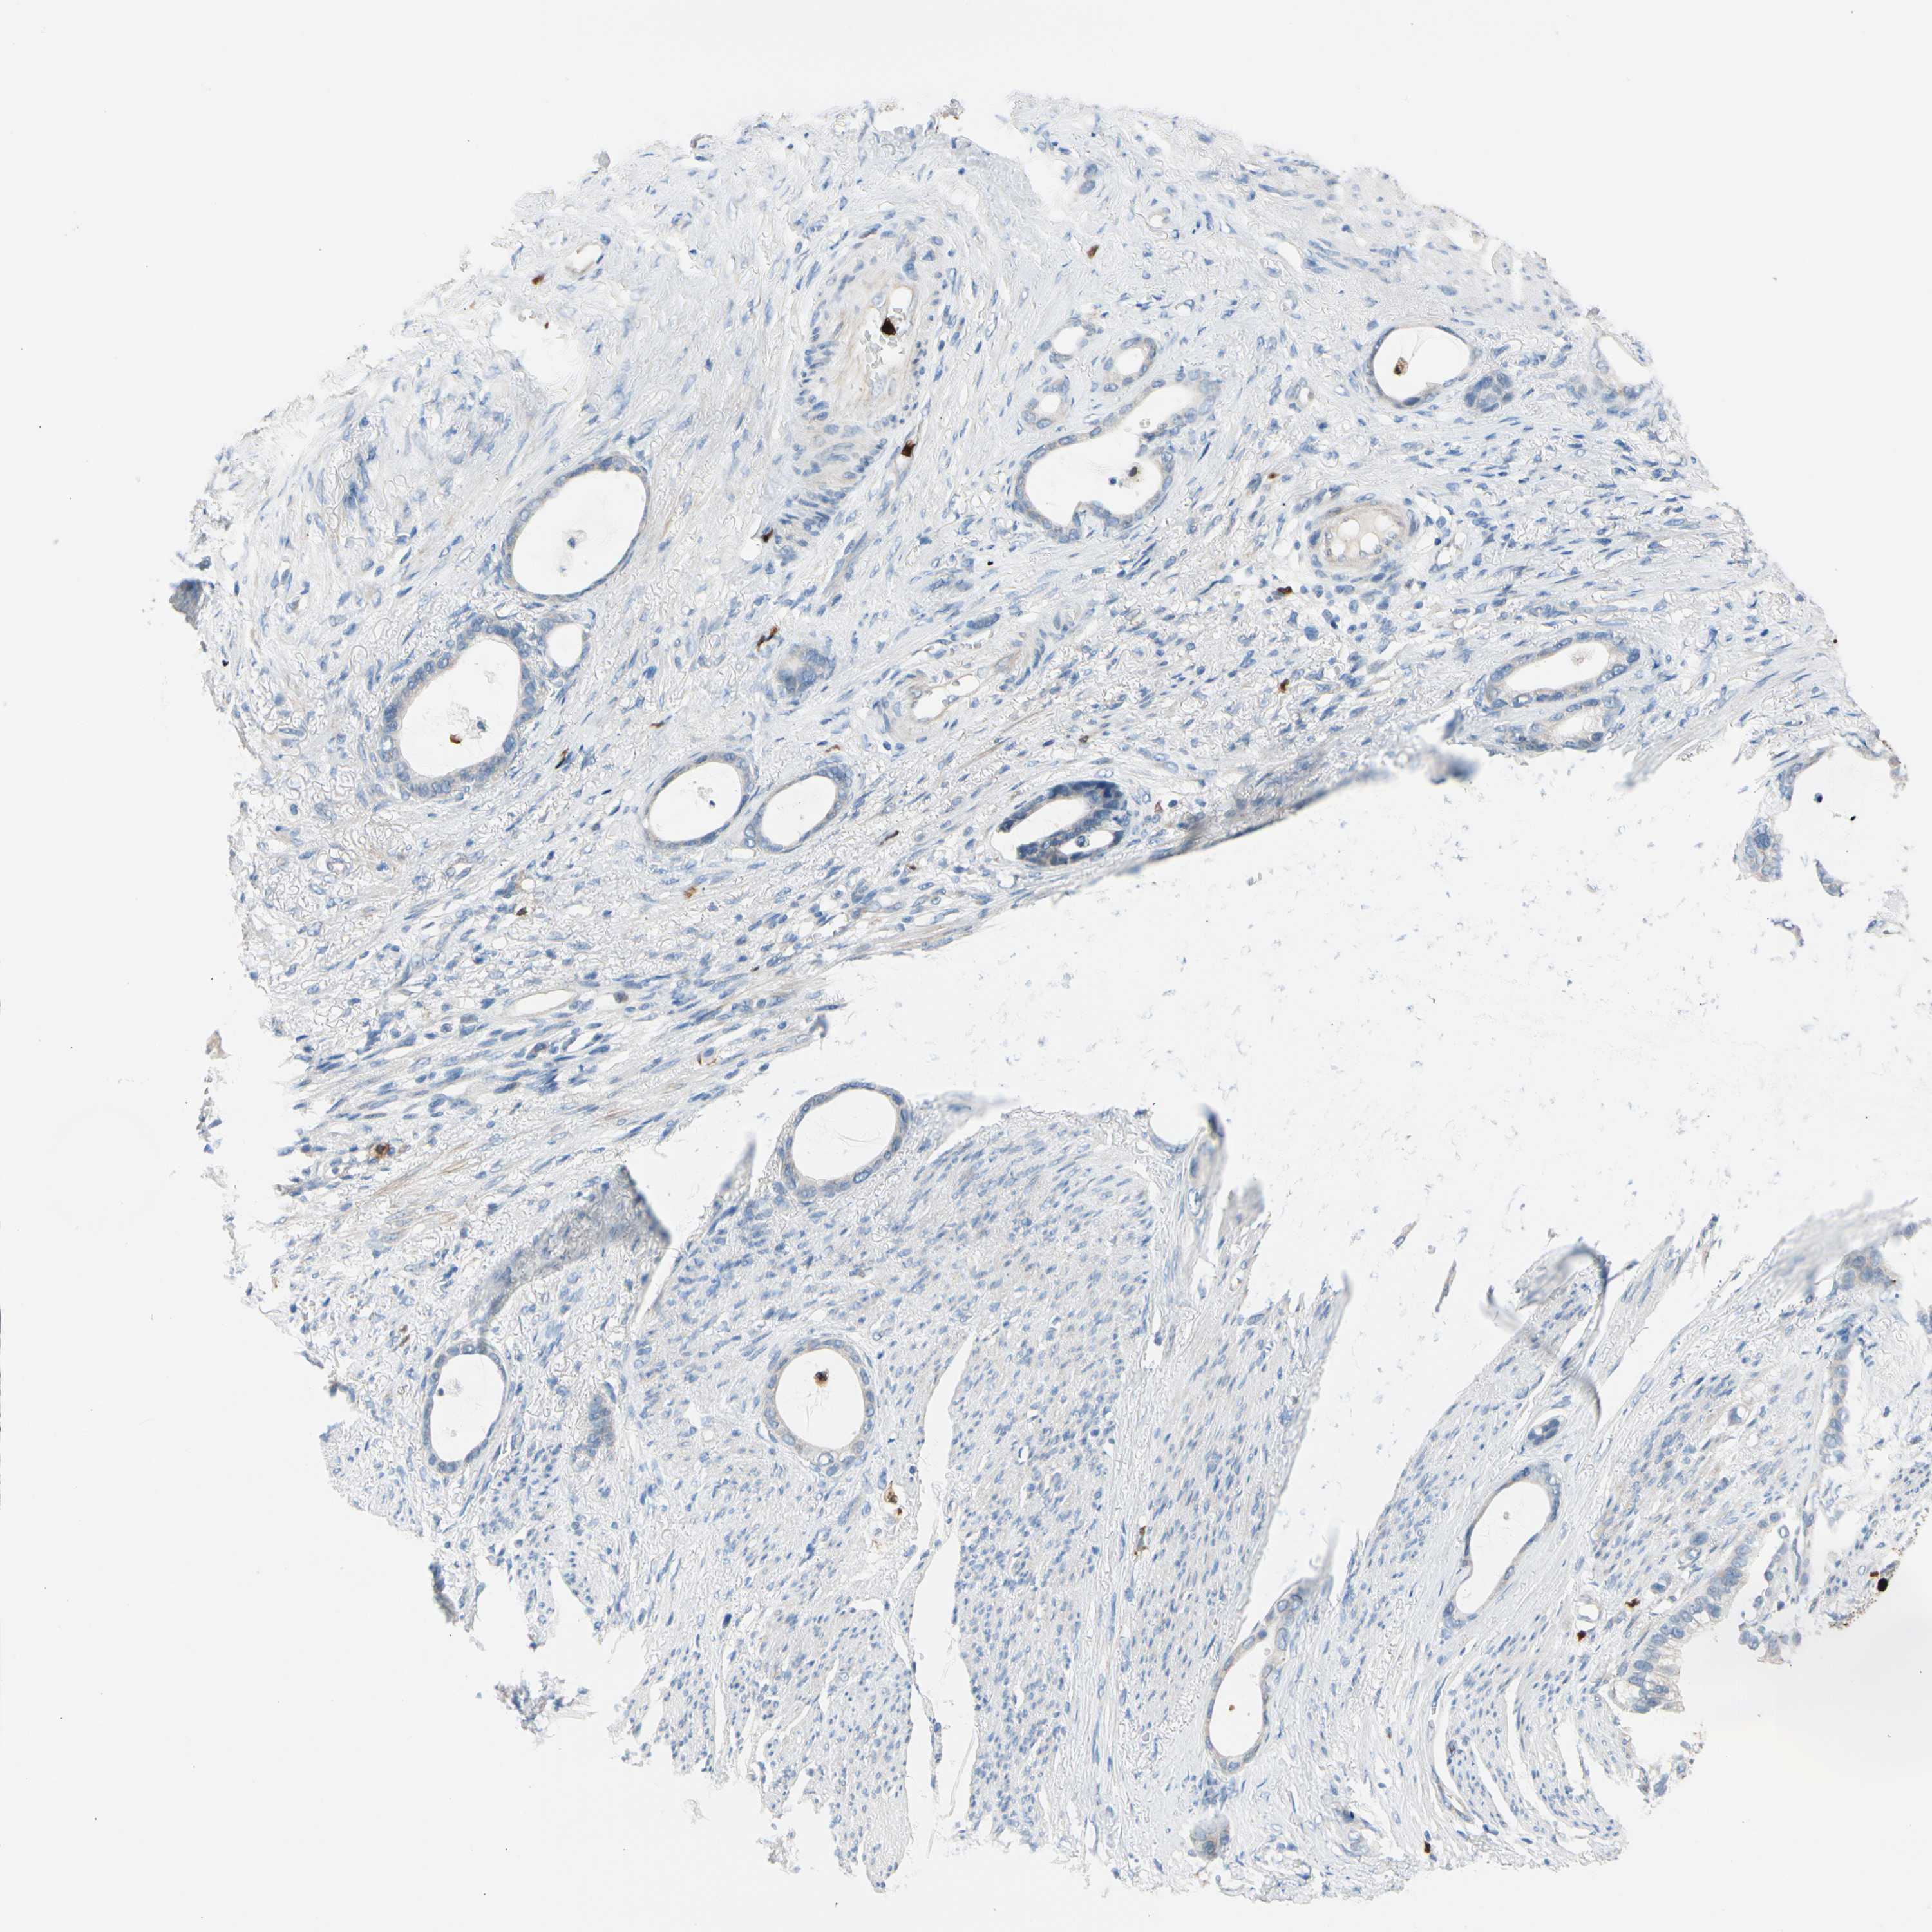

STOMACH CANCER - Protein expressioni

A mouse-over function shows sample information and annotation data. Click on an image to view it in a full screen mode. Samples can be filtered based on level of antibody staining by selecting one or several of the following categories: high, medium, low and not detected. The assay and annotation is described here.

Note that samples used for immunohistochemistry by the Human Protein Atlas do not correspond to samples in the TCGA dataset.

Antibody stainingi

Antibody staining in the annotated cell types in the current human tissue is reported as not detected, low, medium, or high, based on conventional immunohistochemistry profiling in selected tissues. This score is based on the combination of the staining intensity and fraction of stained cells.

Each image is clickable and will lead to virtual microscopy that enables deeper exploration of all samples and also displays staining intensity scores, fraction scores and subcellular localization as well as patient and tissue information for each sample.

Antibody HPA008052

Antibody CAB010277

Staining

High

Medium

Low

Not detected

Intensity

Strong

Moderate

Weak

Negative

Quantity

>75%

75%-25%

<25%

None

Location

Nuclear

Cytoplasmic/membranous

Cytoplasmic/membranous,nuclear

Adenocarcinoma, NOS

Adenocarcinoma, High grade